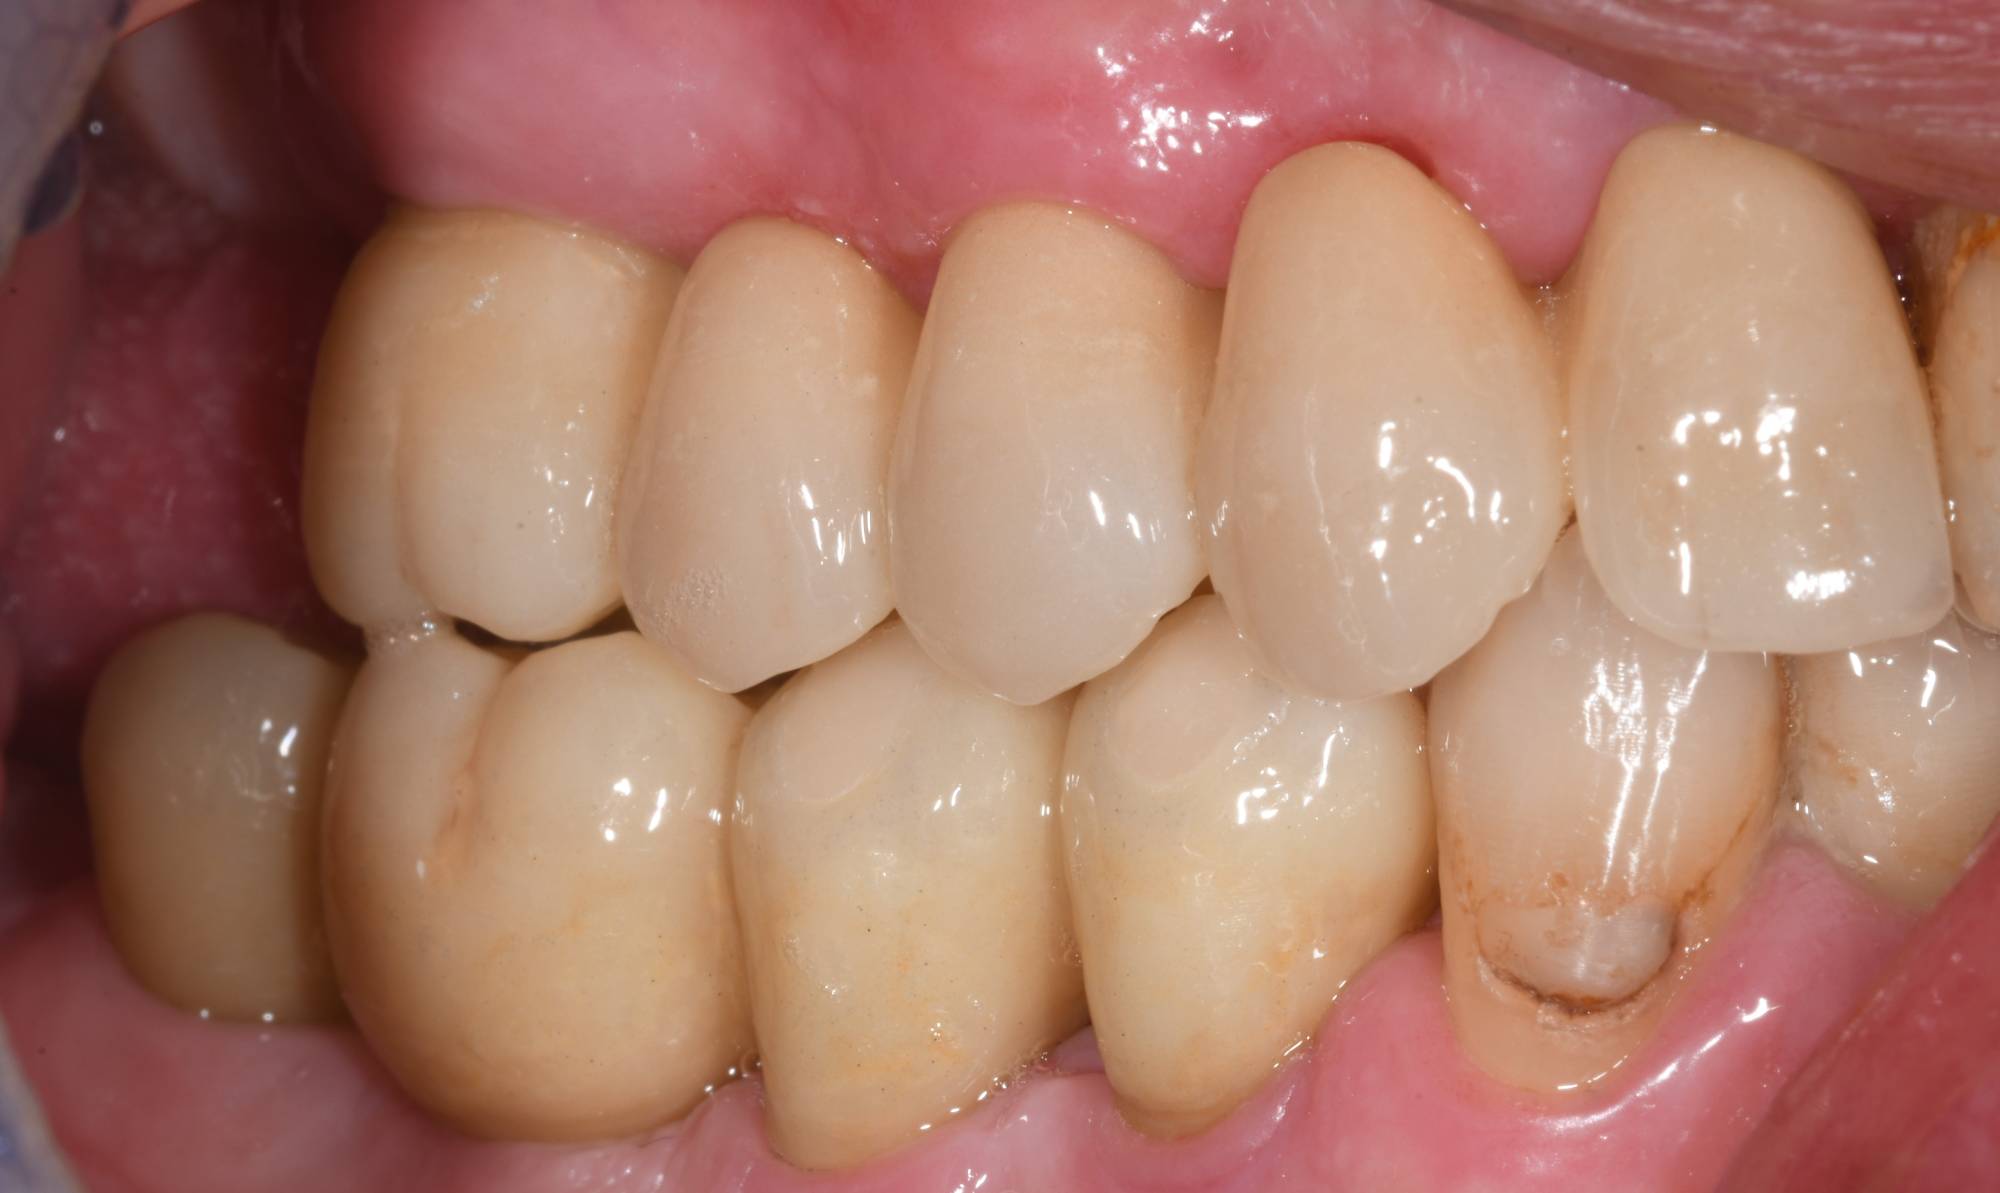

Confronta le foto qui sopra: il paziente necessitava di ripristinare la sua masticazione di destra. Come vedi, nell’arcata superiore aveva vecchie capsule da sostituire e radici da estrarre. Nell’arcata inferiore, due radici da estrarre. Posteriormente era già edentulo, quindi l’unico modo per eseguire una protesi fissa era attraverso quattro impianti, vista l’assenza di pilastri posteriori su cui innestare un ponte fisso.

La prima foto mostra che, comunque vengano sostituiti i denti mancanti, se le corone sono eseguite a regola d’arte, l’effetto è tutto sommato naturale. L’importante è affidarsi ad un odontoiatra che si occupa da anni di odontoiatria estetica, come il dott. Fabio Ballestrasse di Besana Brianza.